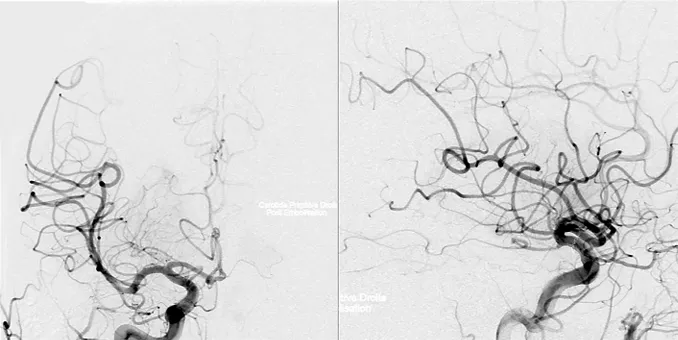

福教授策略:放弃经鼻内镜入路(EEA),选择经后岩骨入路。选择该入路是因为其脑脊液漏的风险有限,并且能够在颞叶下方提供从后到前、从下到上和从外侧到内侧的手术视野,旨在保留位于病变右侧的垂体柄。此外,手术以患者的预后为主要考量要素,而非追求全切。

福教授策略:进行术前栓塞确定供血动脉,且对颅底硬脑膜分支血管的近端闭塞对神经缺血的风险较小。栓塞后的血管造影显示肿瘤的供血动脉重建达到90%,线圈在垂体上动脉内可见(黄色箭头)。

“为了病人而战!”在福教授的手术理念下,这场与垂体细胞瘤的艰难战役正式开启。在福教授的精细操作下,肿瘤慢慢与周围结构分离,同时,为了保留内分泌功能,福教授并未完全切除肿瘤,而是为了保留关键结构,有意沿着垂体柄和视交叉留下了薄薄的残留物,而这也将为安娜醒来后的生活质量打下稳固的基础。

由于进行了术前栓塞,术中并未出现任何出血及并发症,最终这个棘手的肿瘤被成功切除。安娜的预后良好,并在短短一周后出院,期间没有出现新的神经或内分泌功能障碍。组织病理学证实了垂体细胞瘤的诊断。